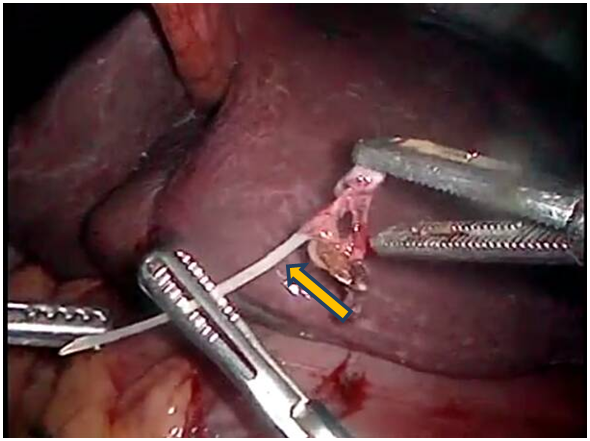

Figure 3 Laparoscopic image showing fish bone in the transcavity of the epiploons (indicated by yellow arrow).

Abdominal ultrasound Figure 1 showed a cystic-looking image with low-level, ecolucent images inside, 20x13mm in diameter, while in double-contrast computed tomography (Figure 2) observed a lesion occupying retrogastric space, towards the transcavity of the epiplons, adjacent to the pancreatic head, hypodense, with poorly defined edges, with attenuation coefficients within the solid and liquid range, 5.6x5.6cm in diameter. In the upper digestive endoscopy a rounded lesion was evident that pushed the posterior face of the heart. A puncture was performed and a purulent liquid was drained from which sample was taken for cytology and culture, which proved to be an inflammatory exudate with abundant polymorphonuclear and basophilic bacterial aggregates (Actynomices). The patient is managed with medical treatment and antibiotic therapy for several weeks under the presumptive diagnosis of complicated pancreatic head tumor with intra-abdominal collection; however, in the persistence of the symptomatology, a diagnostic laparoscopy was planned. During the surgical act when addressing the transcavity of the epiplons, a foreign body was found that came from the stomach (Figure 3), perforating its posterior wall and making contact with the head of the pancreas conditioning a plastron (Figure 4). The foreign body was removed and after a wash and aspiration of the cavity, the surgery was completed.

When the foreign body was examined, it was determined that it was a fish bone, information that was corroborated by the patient when it was reinterrogated and evidenced retrospectively in the tomography performed. The patient presented immediate clinical improvement and after satisfactory evolution he was discharged without eventualities.